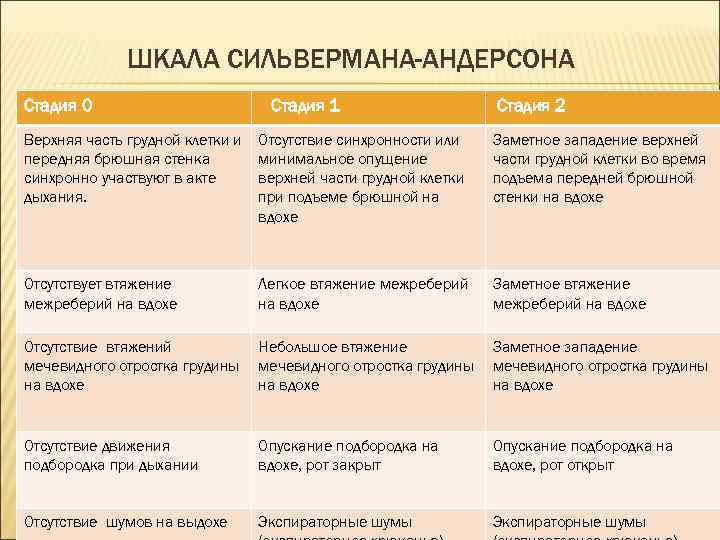

ШКАЛА СИЛЬВЕРМАНА-АНДЕРСОНА Стадия 0 Стадия 1 Стадия 2 Верхняя часть грудной клетки и передняя брюшная стенка синхронно участвуют в акте дыхания. Отсутствие синхронности или минимальное опущение верхней части грудной клетки при подъеме брюшной на вдохе Заметное западение верхней части грудной клетки во время подъема передней брюшной стенки на вдохе Отсутствует втяжение межреберий на вдохе Легкое втяжение межреберий на вдохе Заметное втяжение межреберий на вдохе Отсутствие втяжений мечевидного отростка грудины на вдохе Небольшое втяжение мечевидного отростка грудины на вдохе Заметное западение мечевидного отростка грудины на вдохе Отсутствие движения подбородка при дыхании Опускание подбородка на вдохе, рот закрыт Опускание подбородка на вдохе, рот открыт Отсутствие шумов на выдохе Экспираторные шумы

ДИАГНОСТИКА Диагностика СДР включает определение дефицита сурфактанта в амниотической жидкости ( также в содержимом дыхательных путей или желудка) новорожденного. Его определяют по соотношению лецетин/сфинго, меилин, которое в норме более 3, а при СДР менее 2, 5. Тяжесть СДР определяется по шкале Сильвермана, а также по выраженности других признаков – тахипное, степень цианоза и брадикардией.